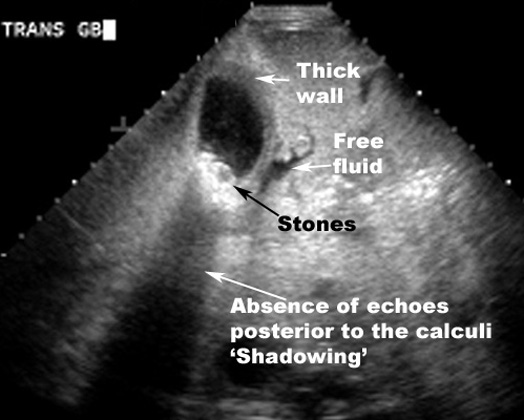

Gallstones - Acute cholecystitiss

US findings:

• Thick GB wall

• Stones in GB

• Absence of echoes posterior to the calculi "Shadowing"